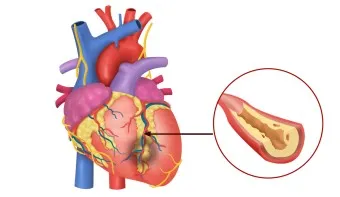

때로는 의학적 관심이 필요한 원인들도 있습니다. 전문가들의 연구에 따르면 다음과 같은 경우를 주의 깊게 살펴봐야 해요:

1. 심장 관련 원인

- 부정맥: 정상 심박수 범위 60-100회/분 이탈

- 심장 판막 이상: 증상 발현 시 심박수 변동 20% 이상

- 빈맥증: 휴식 시에도 심박수 100회/분 이상

- 서맥증: 심박수 60회/분 이하로 저하